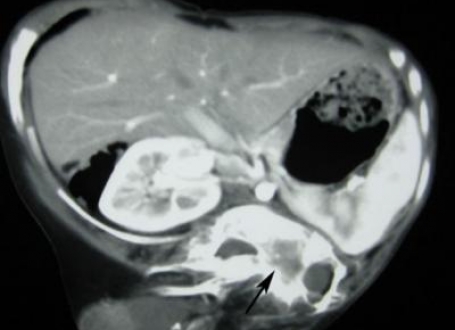

Rendgenski snimak ove genetske anomalije | Foto: Daily Mail

Slučaj fetusa koji se ne razvija vrlo je redak i javlja se jednom u pet miliona slučajeva, a obično se razvije na području abdomena, odnosno u 80 posto slučajeva. Ovo je prvi slučaj zabiležen na leđima.